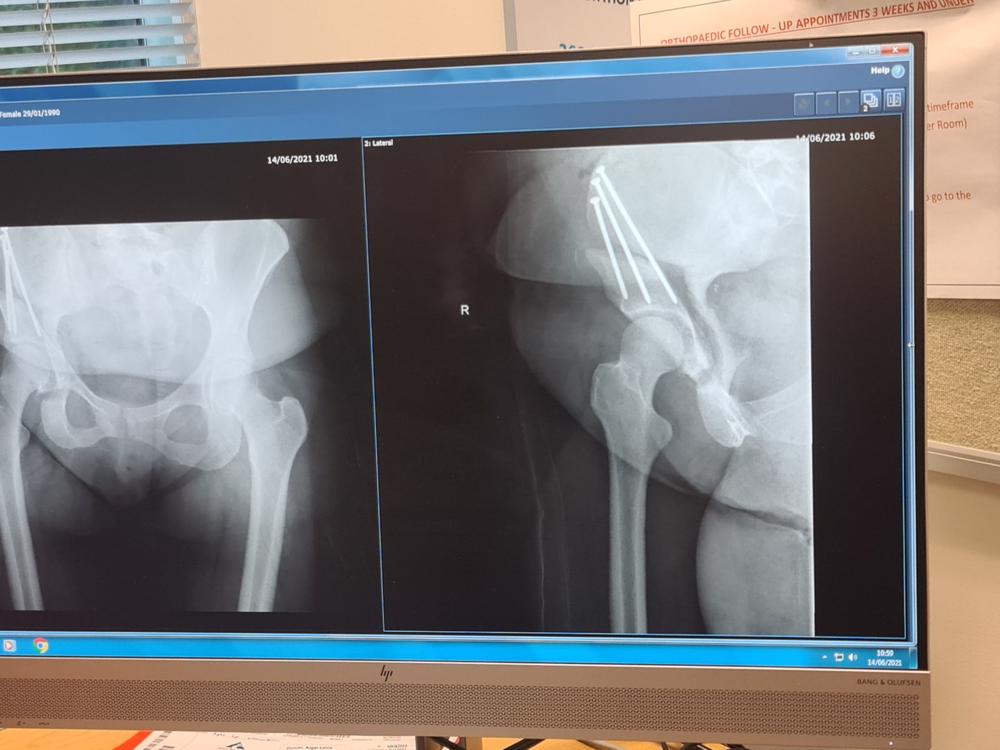

I had a pao surgery in Auckland on May 6th it has not healed so I am on the wait list for a bone graph surgery in Auckland again surgeon and said that I'm on a bone graft list for in the new year. once I've had the surgery I have to travel every 6 weeks back to Auckland for the check ups. But